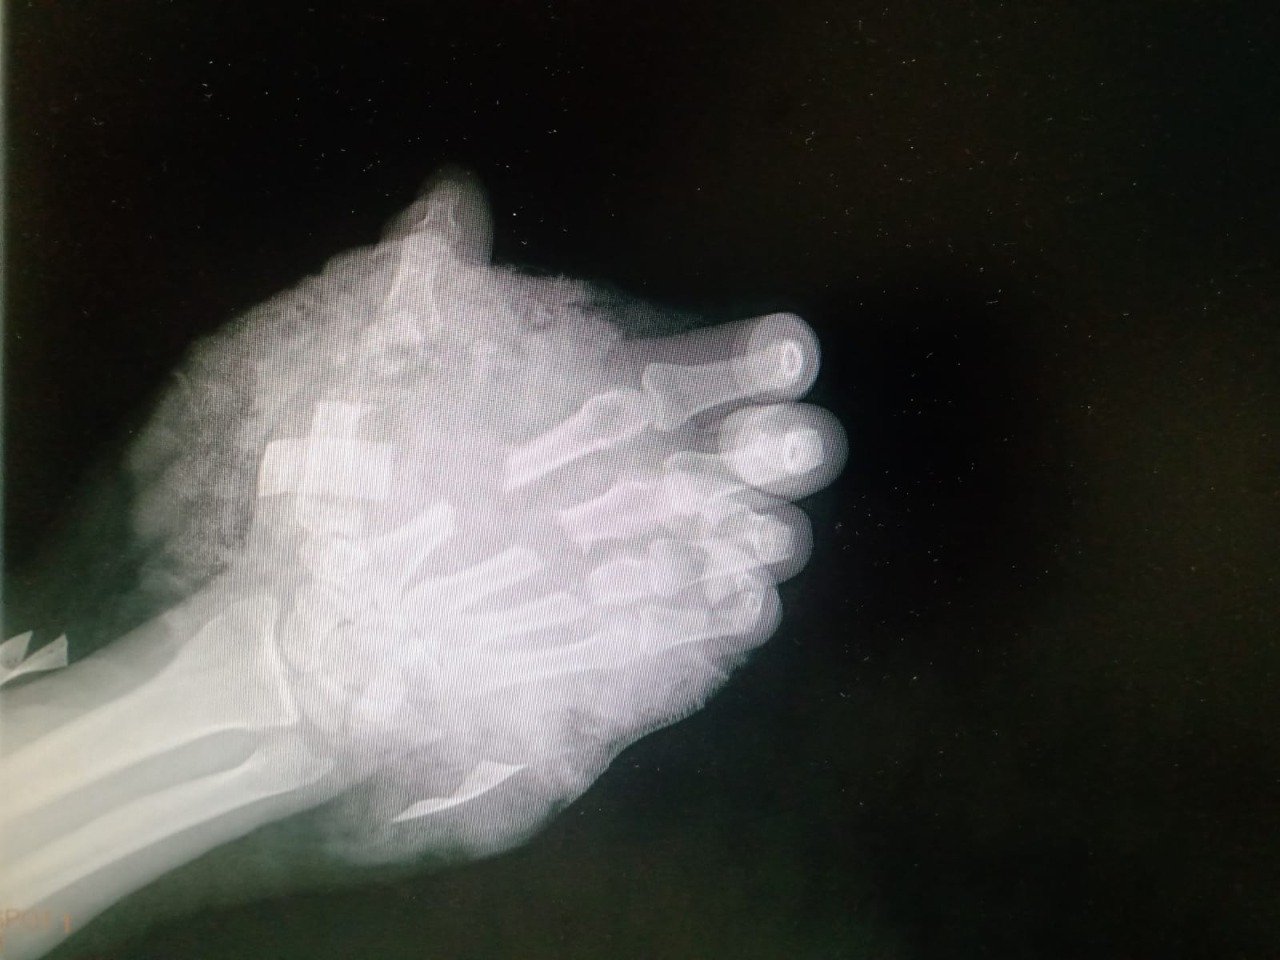

El pasado 15 de abril, Horlando “N” se encontraba terminando su jornada laboral, manejaba una sierra para cortar metal cuando un movimiento inesperado de la herramienta alcanzó la parte superior de su mano derecha.

El sangrado abundante y la apariencia de la herida dejaba ver que se trataba de una lesión grave, motivo por el cual fue trasladado al área de urgencias del Hospital General Regional (HGR) No. 1.

Al recibir los primeros auxilios, se logró detener la pérdida de sangre y se aplicaron antibióticos y analgésicos para evitar una infección y combatir el dolor del paciente. Las características de la lesión llevaron a los médicos a contemplar la posibilidad de una amputación de la mano a la altura de la muñeca.

Sin embargo, el equipo de traumatología del IMSS valoró las opciones para tomar la determinación de estabilizar la extremidad lesionada y programar una cirugía reconstructiva. Los dedos afectados presentaban todavía circulación de sangre dando esperanzas de poder salvarla.